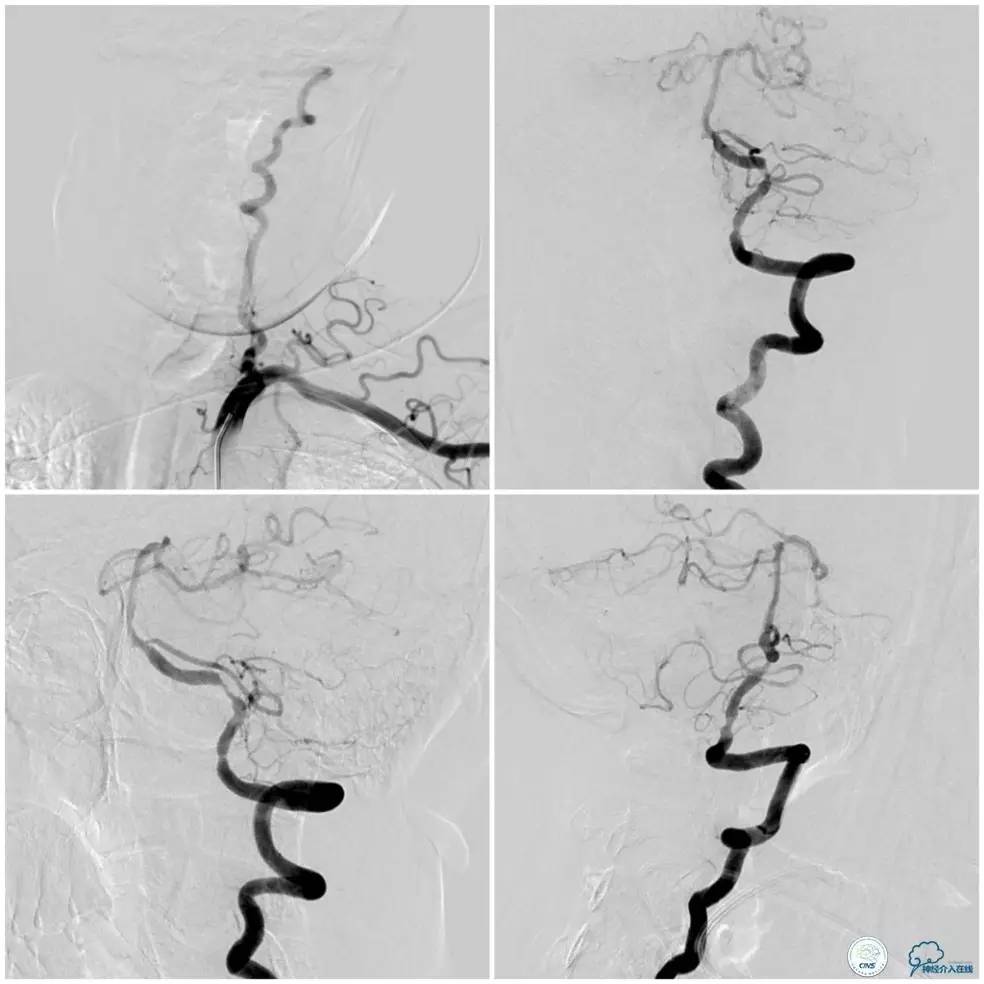

术前DSA:左椎动脉优势,V1及V2段迂曲,V4段狭窄(图5),右椎动脉V2段迂曲(图6)。见右前循环通过后交通动脉向后循环部分区域代偿(图7)。

图5

图6

图7